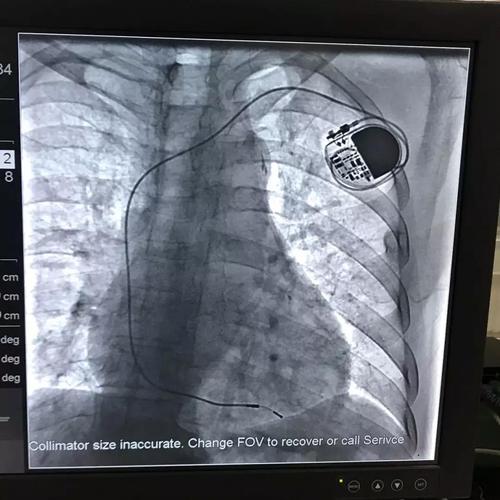

心脏起搏器图片正常

心脏起搏器手术图片

心脏起搏器安装位置图

心脏起搏器图片

安装心脏起搏器图片

心脏起搏器图片实拍